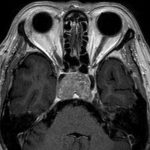

518

'24年3月

20代

眼窩腫瘍

頭蓋内腫瘍摘出術

No.’24_20 手術前1

No.’24_20 手術前2